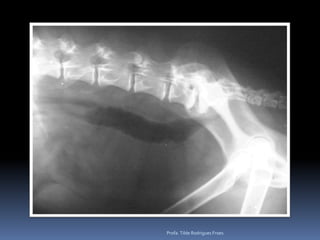

Ex colapsoProfa. TildeRodrigues Froes

Animal: Flick, canino,macho, Poodle, 10 anos - TosseProfa. Tilde Rodrigues Froes